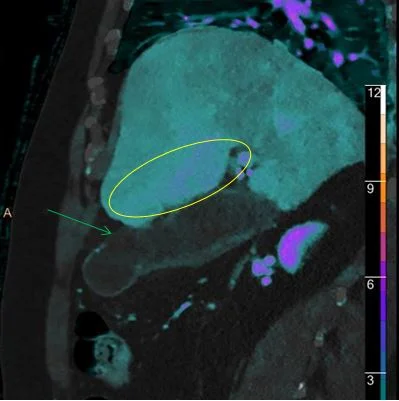

Iodine overlay shows the “hole” very well (green arrow). For nuclear medicine aficionados, see the enhancement in the liver adjacent to the GB fossa (yellow oval), equivalent to the “hot rim sign” so well known from HIDA scans.